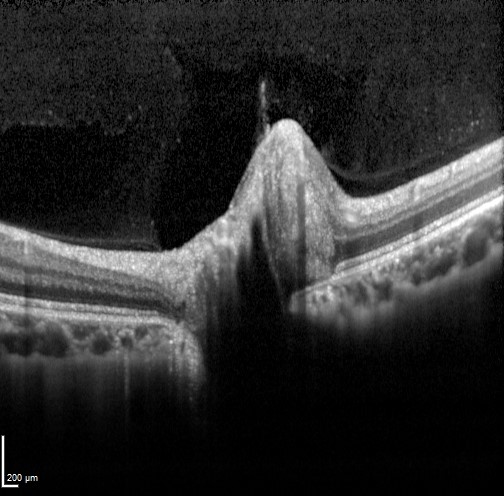

Clinical examination shows a smaller than normal disc with little to no visible cup. Fundus autofluorescence and B-scan ultrasound are unremarkable. OCT imaging shows an apparently elevated optic nerve with no apparent cup and a small Bruch's membrane opening. The retinal architecture adjacent to the optic disc is intact. The nerve may also show a "lumpy bumpy" appearance similar to that created by ONH drusen, however in a crowded disc this is actually due to posterior shadowing caused by the blood vessels trying to enter the small optic foramen. The hypo-reflective areas do not have the hyper-reflective borders seen in disc drusen (further information on disc drusen is available using the tab at the bottom of the page).